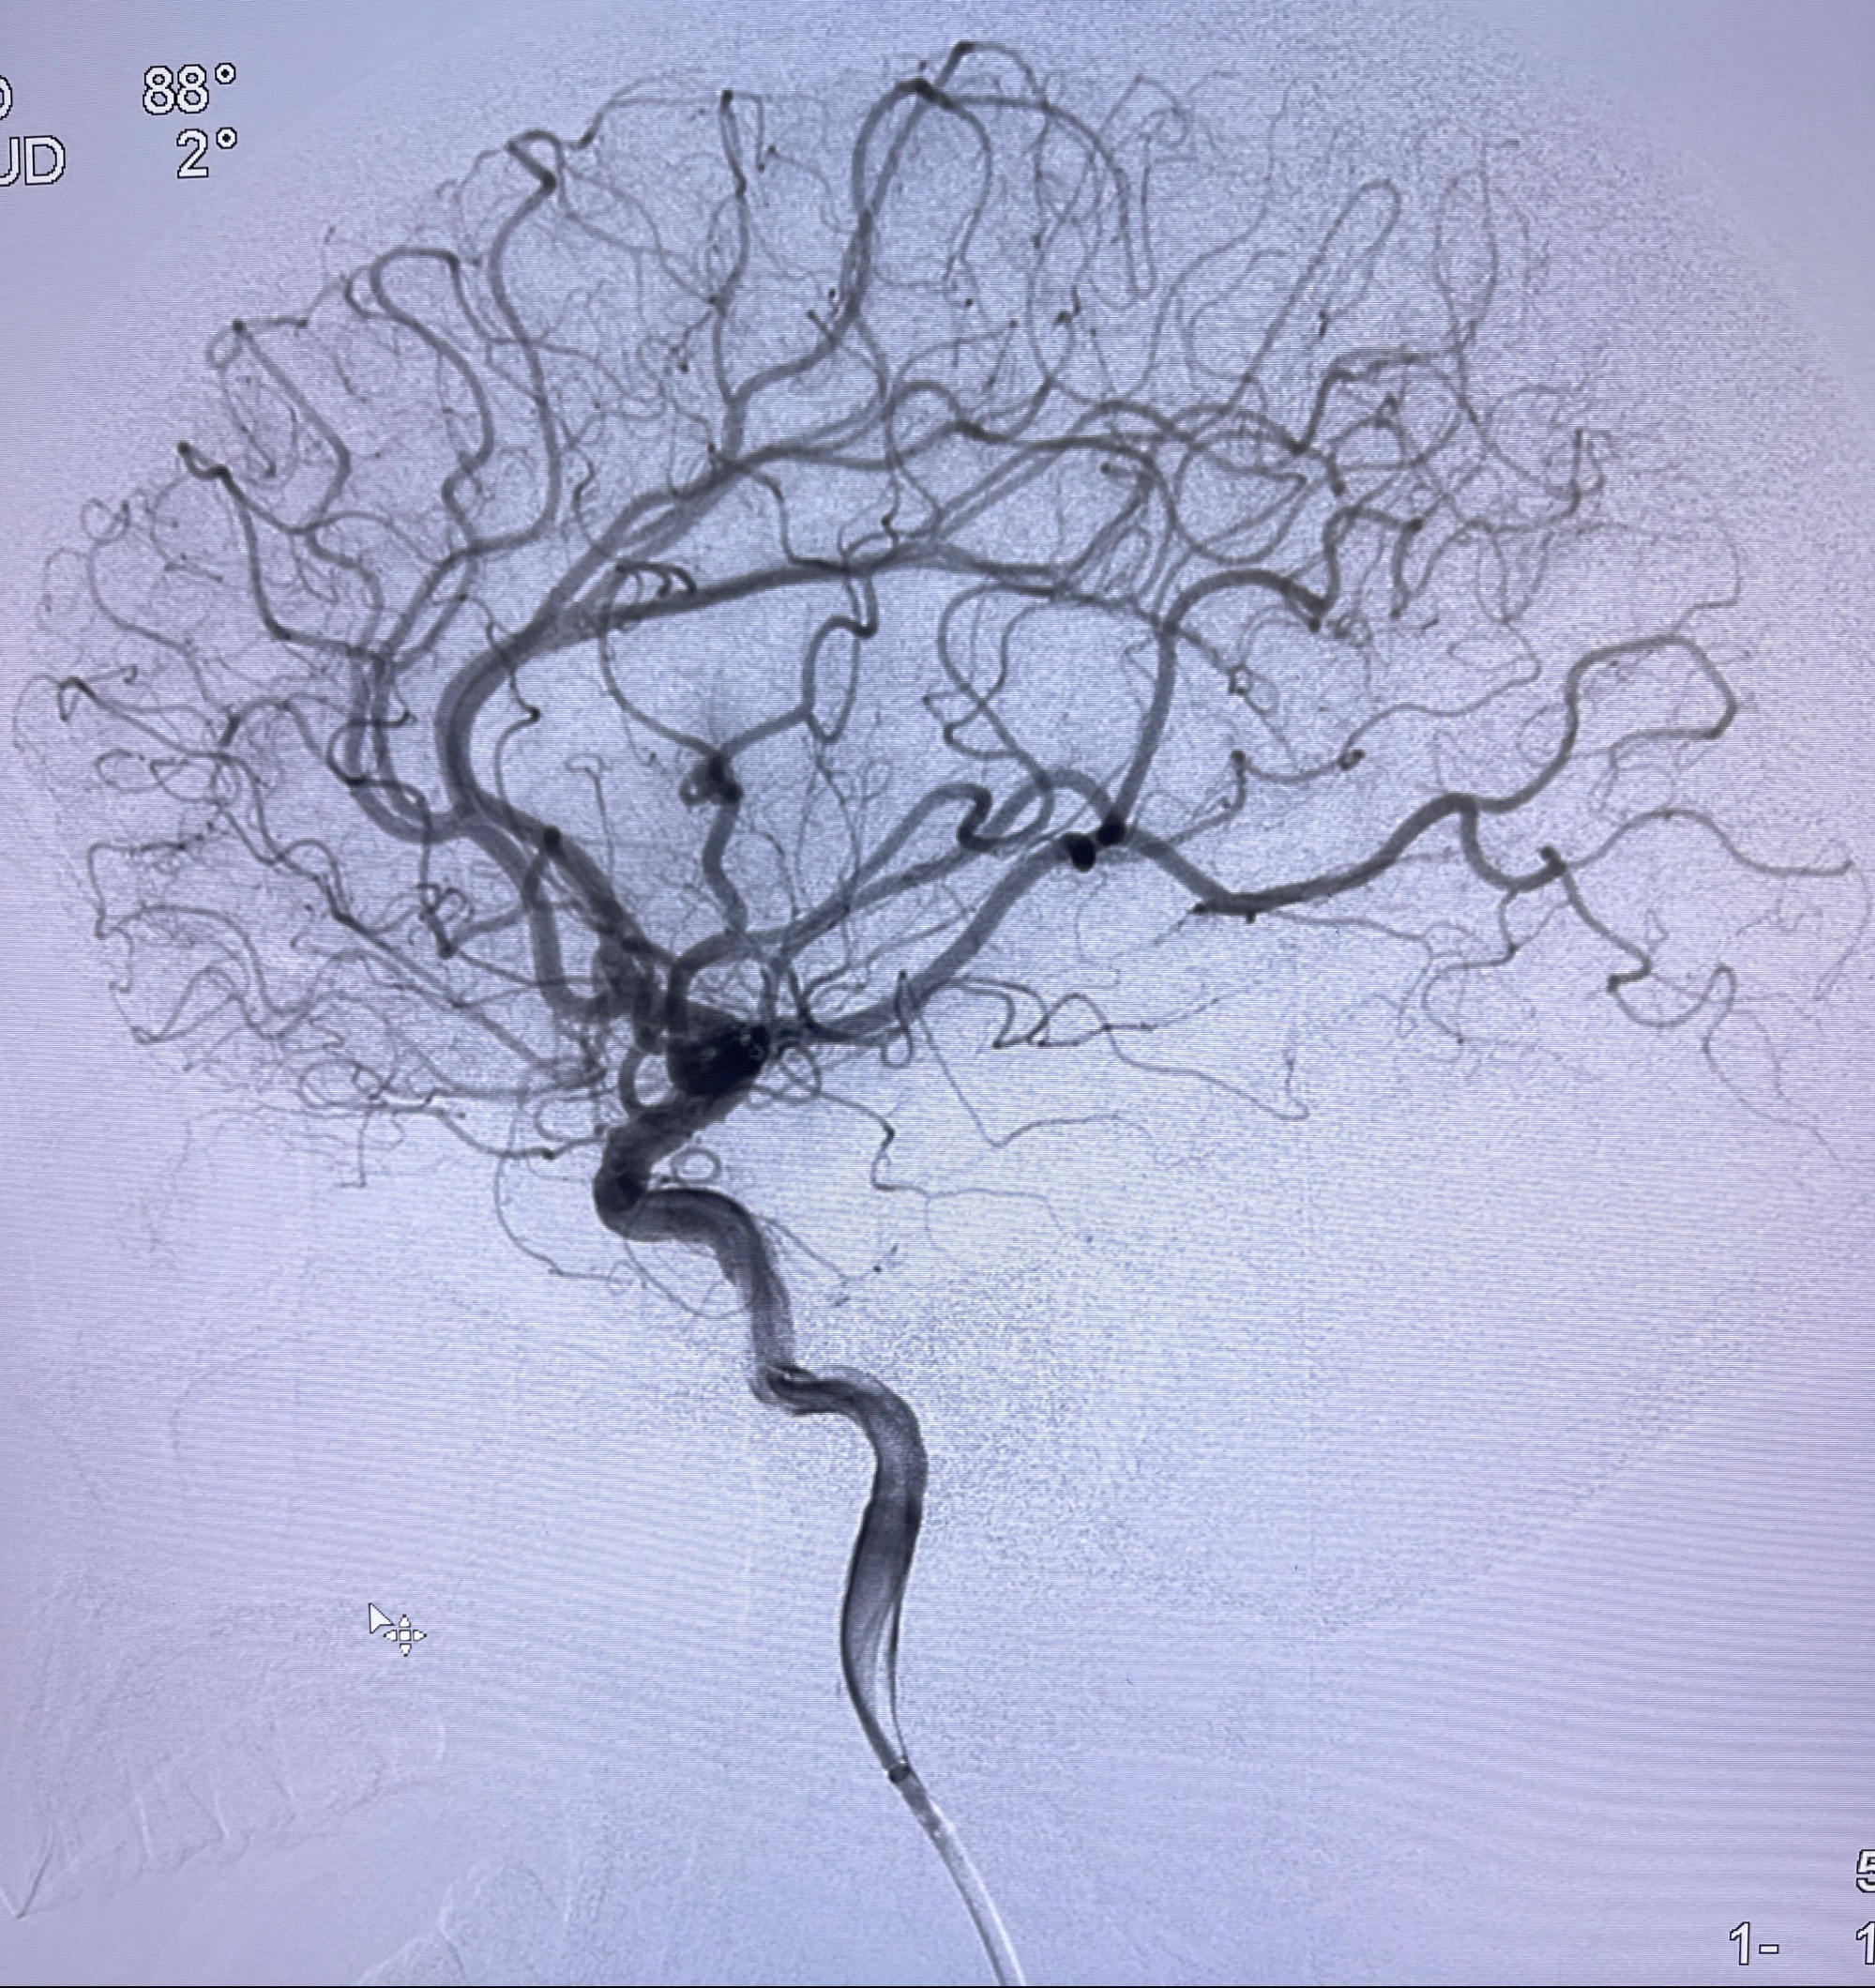

2023-08-14DSA:

左侧大脑中动脉动脉瘤,约2.6-2.8-3.4-2mm大小(瘤颈部、瘤体部、瘤高)

术后即刻CT